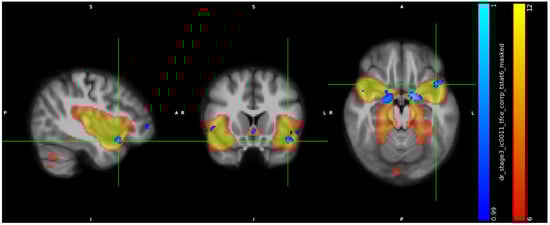

3.2. IC Analysis and Dual Regression

3.3. Neuropsychological Data

3.4. ICA, Neuropsychological Data, and Hormones